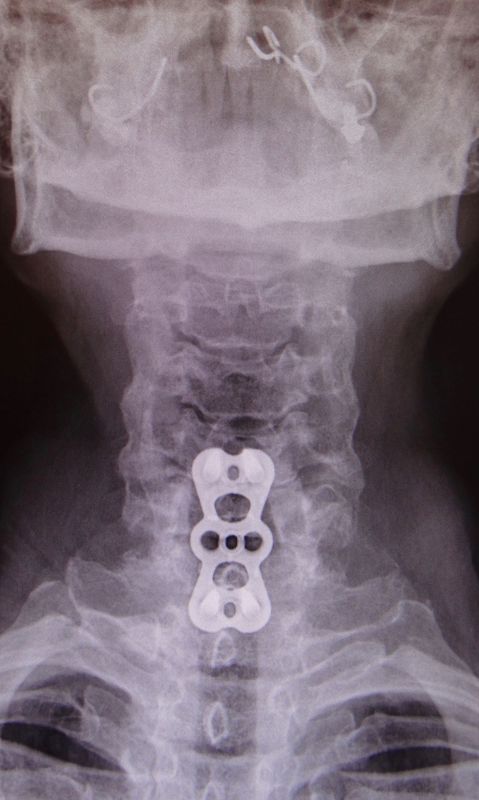

C’est une maladie chronique progressive touchant la moelle épinière. En effet, en raison d’un rétrécissement du canal rachidien (le plus souvent au niveau cervical) par de l’arthrose et des ostéophytes (bec de perroquet) ou un phénomène compressif (hernie discale, kyste, tumeur,…) réduisant le diamètre du canal rachidien, la moelle épinière souffre.

Les symptômes se manifestent par une faiblesse progressive des quatre membres, touchant plus particulièrement les mains avec une perte de la dextérité des doigts, des troubles de la marche, une incontinence urinaire, rarement fécale, et peut évoluer vers la paralysie des bras voire des jambes. C’est une maladie qui évolue lentement dans le temps, sur plusieurs mois, voire années, mais qui peut parfois se décompenser rapidement lors de chute avec mouvement brutal de flexion et extension cervicale.

Le traitement consiste, dans la plupart des cas, en une chirurgie de décompression de la moelle épinière par discectomie cervicale antérieure et mise en place d’une cage avec plus ou moins une plaque/vis stabilisatrice. Malheureusement, il n’existe pas de traitement conservateur, excepté le soulagement des douleurs. Il est important d’opérer rapidement au moment du diagnostic afin d’éviter une aggravation de la faiblesse des 4 membres.